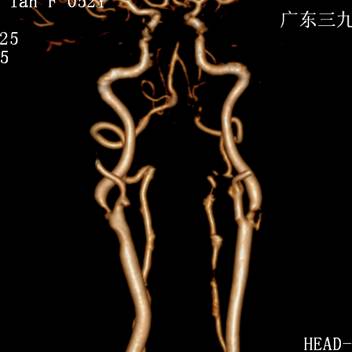

1周前,郭大姐再次发生右侧肢体无力的症状,于是家人将她送到广东三九脑科医院神经内科就诊,入院后积极完善相关检查,颅脑DWI显示:1、左侧基底节区、大脑脚及桥脑右侧、右侧枕叶多发陈旧性脑梗塞,2、考虑胼胝体压部偏左侧脑梗塞(偏慢性期)(如图1、图2)。DSA检查提示:1. 基底动脉末端闭塞,双侧大脑后动脉、后交通动脉未见显影,双侧大脑中动脉经皮层软膜动脉向同侧枕叶代偿供血;2. 双侧颈内动脉起始部重度狭窄(如图4、图5),狭窄率约90%,狭窄长度约20px;3.双侧椎动脉起始部中度狭窄,狭窄率约50%;4. 脑动脉硬化,颅内动脉走行僵硬,呈不同程度狭窄。

图 3 术前CTA提示:双侧颈内动脉起始部重度狭窄;